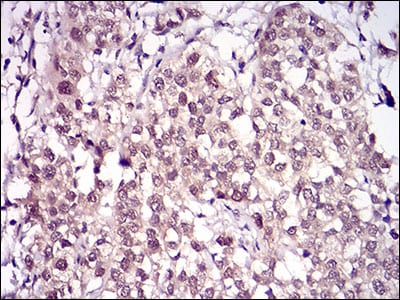

Immunohistochemical analysis of paraffin-embedded human cervical cancer tissues using RANBP9 mouse mAb with DAB staining.